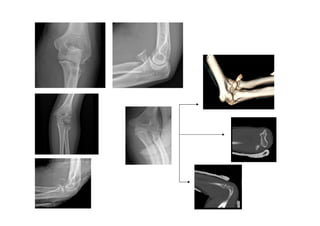

5.1 Fracturas de húmero distal

• 0.5 % de todas las fracturas

del adulto.

• Se consideran fracturas de

húmero distal aquellas cuyo

epicentro se localiza en el

cuadrado de Muller.

• Edad:

– Adulto: fracturas supra-

intercondileas, conminutas

por traumatismo directo.

– Niños: fracturas

supracondileas por traumas

indirectos

Clasificación:

5.2 Fracturas de cabeza de Radio:

• 20-30% de las fracturas del

codo.

• Mecanismo lesional:

Generalmente traumatismos

indirectos al caer sobre la

mano en extensión.

• Clínica: dolor selectivo a la

palpación de la cabeza de

radio, que se acentúa con la

prono-supinación

• Clasificación de Mason

5.3 Fracturas de olécranon:

– Mecanismo lesional:

Impacto directo sobre el

olécranon con el codo en flexión.

– Dolor, tumefacción, edema sobre

el olécranon, clínica por

afectación del nervio cubital.

Palpación de un surco en el lugar

de la fractura.

– Impotencia para extensión de

codo contra gravedad

Clasificación de Colton:

5.4 Luxaciones de codo

• Clínica:

– Tumefacción, dolor y pseudoparálisis

brazo.

– Deformidad codo

– Exploración vasculonerviosa : arteria

braquial

• Tipos:

– Luxación posterior: la más frecuente

(caída con brazo extendido).

Olécranon a posterior.

– Luxación anterior: rara. Suele ser

abierta, vigilar desgarro art. Radial.

– Luxación divergente: muy rara.

– Fracturas – luxaciones.

• Trto:

– Reducción cerrada

– Inmovilización tres semanas y citar en

cext. traumatología 3 sem.